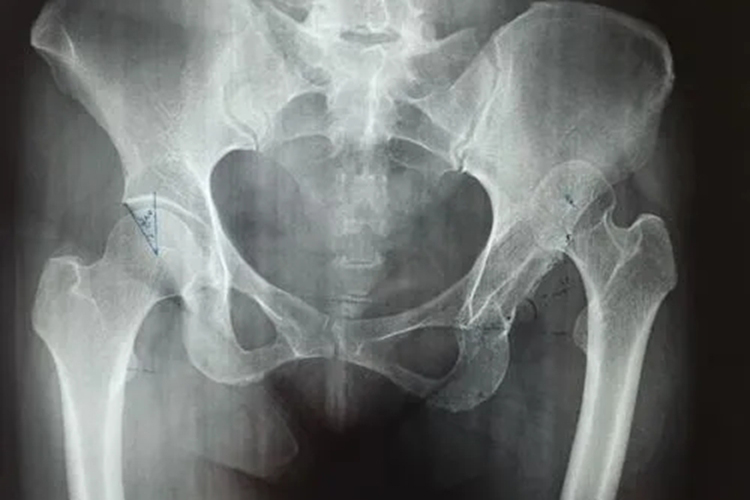

髋关节脱位

主要表现为患侧髋部疼痛,关节活动障碍。体格检查可见患侧下肢呈屈曲、内收、内旋和短缩畸形。可在臀部摸到脱出的股骨头,大粗隆上移明显。X线检查可见脱位的情况。